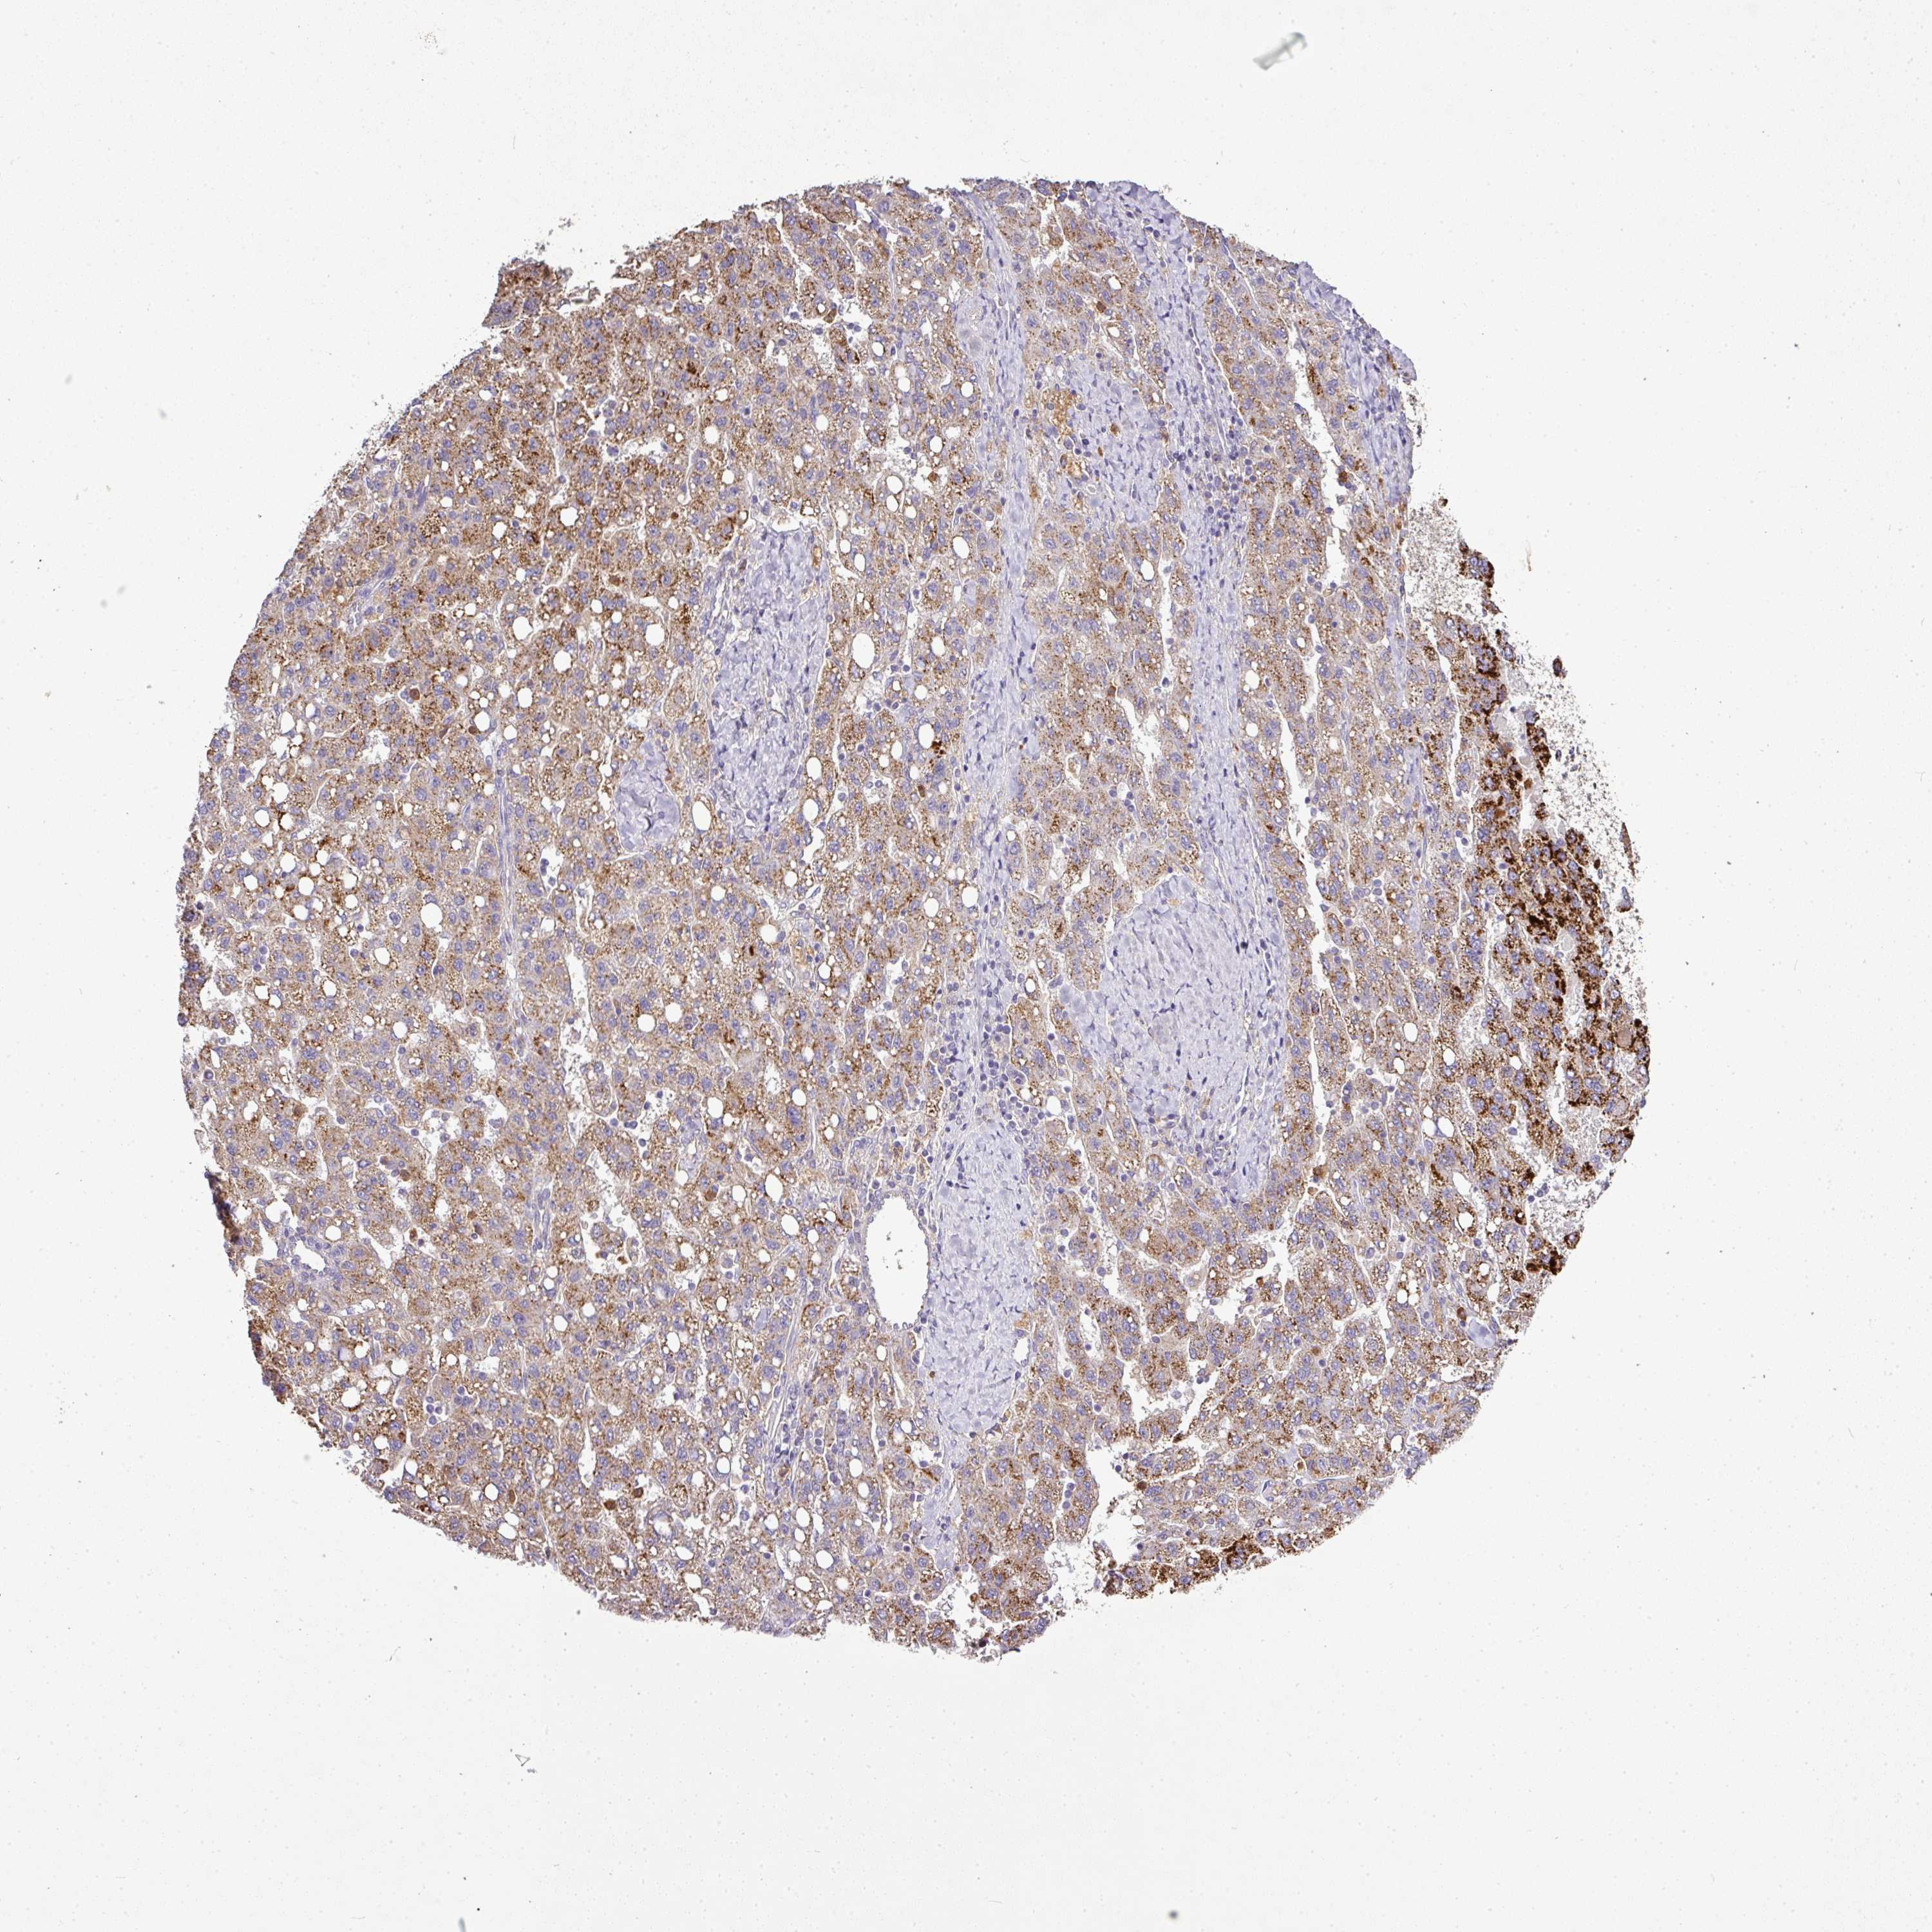

LIVER CANCER - Protein expressioni

A mouse-over function shows sample information and annotation data. Click on an image to view it in a full screen mode. Samples can be filtered based on level of antibody staining by selecting one or several of the following categories: high, medium, low and not detected. The assay and annotation is described here.

Note that samples used for immunohistochemistry by the Human Protein Atlas do not correspond to samples in the TCGA dataset.

Antibody stainingi

Antibody staining in the annotated cell types in the current human tissue is reported as not detected, low, medium, or high, based on conventional immunohistochemistry profiling in selected tissues. This score is based on the combination of the staining intensity and fraction of stained cells.

Each image is clickable and will lead to virtual microscopy that enables deeper exploration of all samples and also displays staining intensity scores, fraction scores and subcellular localization as well as patient and tissue information for each sample.

Antibody HPA045954

Antibody HPA076632

Antibody CAB003686

Staining

High

Medium

Low

Not detected

Intensity

Strong

Moderate

Weak

Negative

Quantity

>75%

75%-25%

<25%

None

Location

Nuclear

Cytoplasmic/membranous

Cytoplasmic/membranous,nuclear

Carcinoma, Hepatocellular, NOS

Cholangiocarcinoma

Adenocarcinoma, NOS